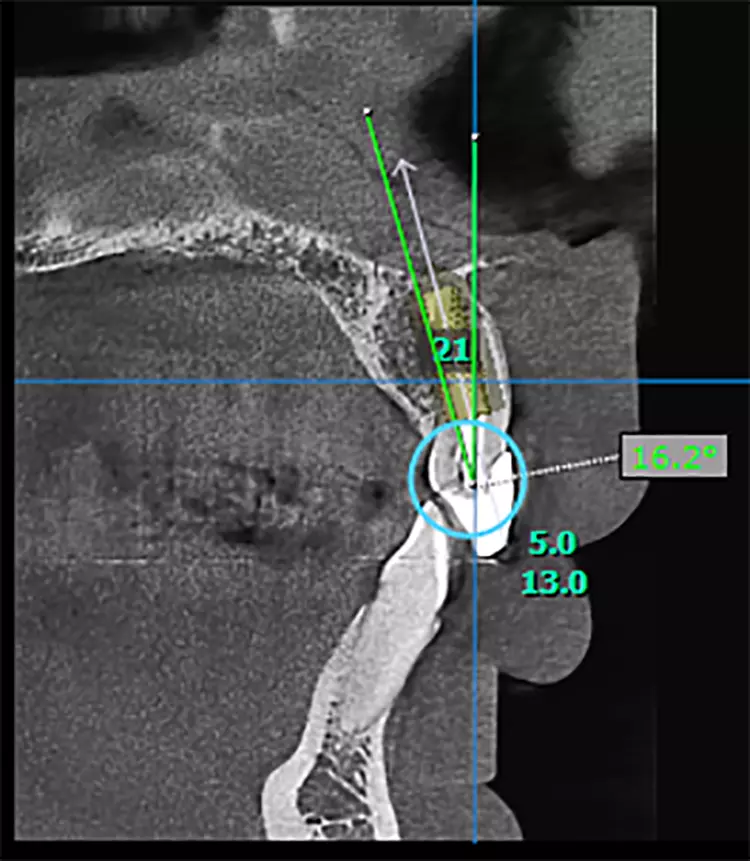

Bei diesem 49-jährigen, allgemeinanamnestisch unauffälligen Patienten liegen diverse ästhetisch störende Zahnstellungsanomalien vor, wobei Zahn 21 bei extremer Elongation frakturierte (Abb. 2a). Nach einer Übergangsversorgung mittels provisorischer Stiftkrone (Abb. 2b) entschied sich der Patient für eine Zahnentfernung bei gleichzeitiger Implantation. Im Ausgangs-DVT (Abb. 2c und d) zeigt sich im Cross-Sectional, wie weit der Processus alveolaris zurückliegt.

In solchen Fällen empfiehlt sich daher die Anwendung einer Bohrschablone im Sinne der Guided Surgery. Liegen solche anatomischen Besonderheiten nicht vor, so wie es meist im Prämolarenbereich der Fall ist, kann die Bohrung mittig, der Alveole folgend vorgenommen werden (siehe Fall 1). Dabei ist anzumerken, dass vor allem bei Implantation des ersten oberen Prämolaren gern die palatinale Alveole genutzt wird, um die Entlastung der vestibulären Lamelle zu garantieren.